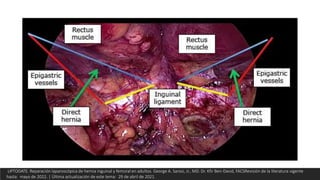

TAPP

 Colocación de una malla en una posición

preperitoneal, que está cubierta por peritoneo

para mantener la malla alejada del intestino.

Tiene un espacio de trabajo más grande que la

TEP, con fácil acceso a ambas ingles, y puede

intentarse en pacientes con cirugía abdominal

inferior previa.

UPTODATE. Reparación laparoscópica de hernia inguinal y femoral en adultos. George A. Sarosi, Jr., MD. Dr. Kfir Ben-David, FACSRevisión de la literatura vigente

hasta: mayo de 2022. | Última actualización de este tema: 29 de abril de 2021.